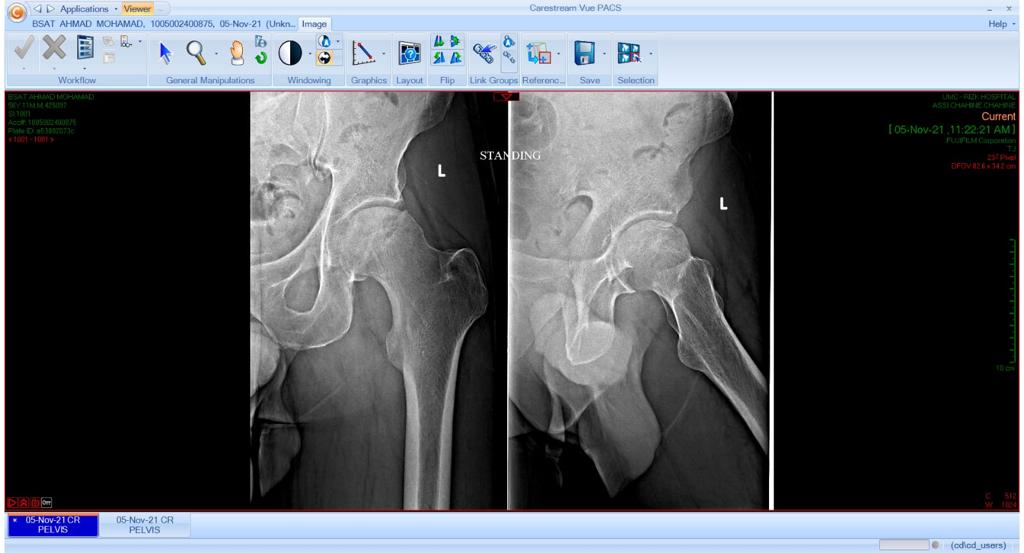

Total Hip Arthroplasty Anterior Approach